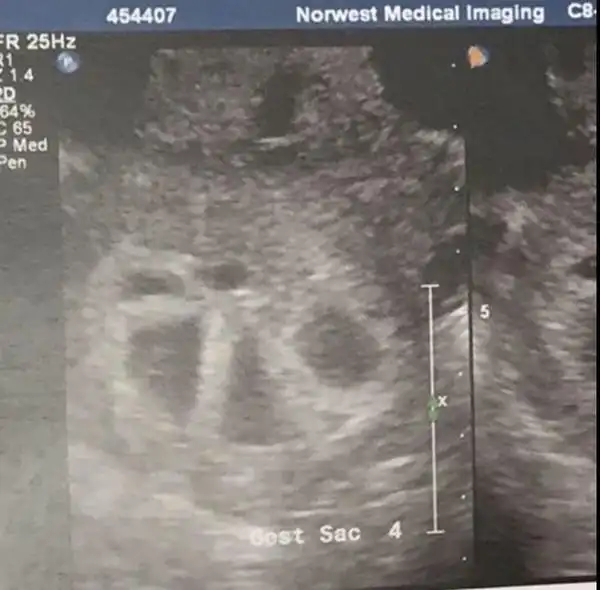

Так выглядит женщина, беременная пятерняшками

Австралийка Кимберли Туччи и ее муж в течение года не могли забеременеть долгожданным третьим ребенком, а когда это произошло, пара узнала, что у них будут пятерняшки. Шансы зачать пятерняшек составляют один к 55 миллионам, однако, супруги смогли это сделать и теперь готовятся к пополнению.